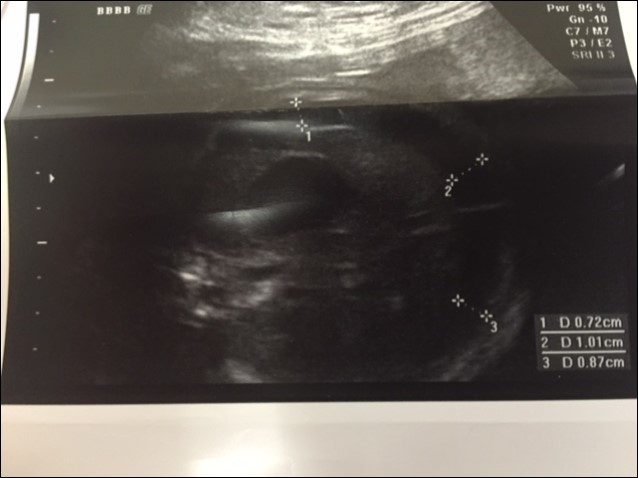

A 37 year old G3P2 female was referred to the pediatric surgical clinic for a twin pregnancy with one of the twins having a large left sided lung mass. The mother had a BMI of 48 and had undergone lap band surgery in the past. The lung mass was detected at 22nd week of gestation and was noted to be homogenous and solid on ultrasound and had a Cyst Volume Ratio (CVR) of 1.4. The twins were dichorionic diamniotic. Twin A had a posterior placenta and twin B (twin with the lung mass) had an anterior placenta. The lesion was located in the left hemi thorax and did not have any associated pleural effusion at first. The differential diagnosis for this lesion included a Stoker Type3 CPAM, a mediastinal teratoma, and a diaphragmatic hernia6. The Twin B was superior in the uterus in a breech position to the right side with a vertical pocket of amniotic fluid measurement of 6.8cm. The Bio Physical Profile score was 10/10. While the middle cerebral artery and ductus venosus dopplers were normal, there was some drop off in the end diastolic flow in the umbilical artery Dopplers. The mother was placed on weekly hi-definition ultrasound follow ups. Echocardiogram showed no structural cardiac defect. Steroids (betamethasone 12mg IM, two doses, 24hours apart) were administered after the development of pleural effusion was noted at the repeat ultrasound performed at 24 weeks and at this point CVR had increased to 1.6. As there was an inadequate response to steroid administration, with the development of a mediastinal shift from the mass effect of the lesion and significant pleural effusion, aspiration of the pleural fluid was performed twice (at weekly intervals during the 26th and 27th week of gestation) with recurrence of the effusion. The pleural fluid analysis showed that it was transudate on both occasions. The volume aspirated on each occasion was about 20 ml. Ascites was also detected and 10 ml of abdominal fluid was aspirated during the second aspiration. It appeared that the fetus was developing hydrops. During the 30th week ultrasound showed a significant mediastinal shift to the right, a large liver with ascites, and increased fetal skin thickness. A thoraco-amniotic shunt was placed at the 30th week of gestation and another course of steroids administered Figure 1 and Figure 2. The significant maternal subcutaneous fat would allow only a direct lateral access into the pleural cavity. The twin and mother were doing well with no symptoms. However, three weeks later, the fetus was able to dislodge the 'double-J' catheter and a second thoraco-amniotic shunt was placed because of recurrence of pleural effusion. While this was successful initially, the combination of the twin pregnancy and interventions led to premature delivery of the twins at 34 weeks gestation. MRI was not considered in the evaluation because of the large BMI.

Figure 1.Antenatal Ultrasound demonstrating the guide wire and shunt in position. The thickness of the amniotic fluid is being measured by the markers.